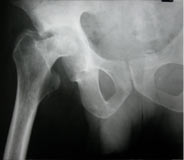

Koch's hip-arthritic jt.

Koch's hip mortar & pestle type

Koch's hip mortar & pestle type xray2